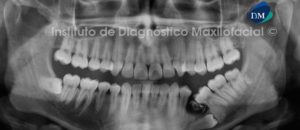

Paciente masculino de 65 años de edad es referido al Instituto de Diagnóstico Maxilofacial (IDM) para evaluación de problemas periodontales. A la evaluación de la radiografía panorámica se aprecia una imagen radiopaca de densidad de tejidos blandos, de forma redondeada proyectada en el antro del seno maxilar izquierdo, compatible con quiste de retención mucoso. Asimismo observamos reabsorción ósea alveolar moderada generalizada, con presencia de proceso osteolítico peri radicular a nivel de pieza 3.7 (Figura 1).